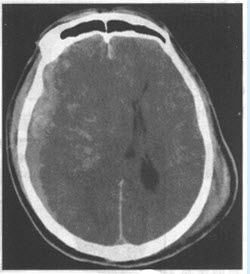

男,77岁,右侧肢体活动不灵伴昏迷1天余,右侧病理征(+),平扫CT检查如图,最可能的诊断为()

A:脑出血

B:脑梗死

C:脑炎

D:脑胶质瘤

E:脑转移瘤